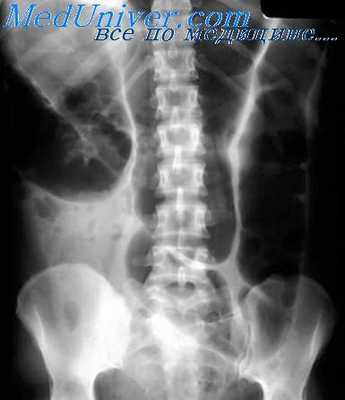

Воспалительно-деструктивные процессы. Деструкция стенки кишки, вызванная язвенным процессом (в частности, при язве двенадцатиперстной кишки, язвенном энтерите или колите), проявляется при рентгенологическом исследовании симптомом ниши, которая может иметь вид контрастного пятна (депо бария), окруженного воспалительным валом, либо конической формы выступа на контуре кишки (профильная ниша). При этом нередко наблюдается конвергенция складок слизистой оболочки к нише.

Язвенный процесс в кишке, как правило, сопровождается ее деформацией, обусловленной локальным спазмом, воспалением и отеком слизистой оболочки в зоне расположения язвы (или язв), а также Рубцовыми и спаечными процессами. В отличие от распадающейся опухоли язва в кишке имеет небольшие размеры, инфильтративный вал у ее основания симметричен, а степень деформации кишки в зоне поражения в процессе исследования, особенно при применении дозированной компрессии и спазмолитических препаратов, меняется в значительных пределах. Величина и форма язвенной ниши остаются стабильными.

Проводя дифференциальную диагностику язвы и дивертикула, исходят прежде всего из того, что стенки его в отличие от язвенного кратера эластичны, сохраняют способность к сокращению, участвуют в перистальтике кишки. Инфильтративный вал у основания дивертикула отсутствует, а складки слизистой оболочки переходят в его шейку.